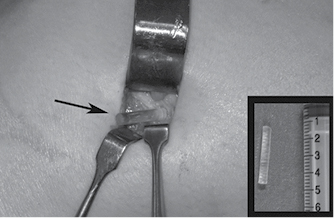

Se decidió realizar procedimiento quirúrgico para retiro de pin bioabsorbible; en el procedimiento se observó extrusión de 1 cm del pin con borde cortante reductible (Figura 3) y al retirarlo se observó presencia de ruptura del pin (Figura 4). Posterior a la cirugía se corroboraron arcos de movimiento completos (0o-120o) con adecuada estabilidad ligamentaria. Se continuó vigilancia del paciente, con rodilla izquierda sin presencia de dolor o derrame articular, con arcos de movimiento completos, sin datos de inestabilidad, tolerando actividad física y con escalas de funcionalidad adecuadas.

Figura 3: Imagen quirúrgica de la porción del pin bioabsorbible protruida hacia la región lateral extraarticular. En la esquina inferior derecha se observa la porción fracturada del pin retirada en cirugía.